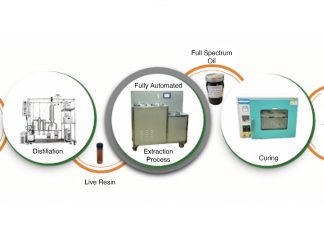

Inflammacheck®, launched in 2019, is a new handheld point-of-care test which can quickly measure hydrogen peroxide levels in exhaled breath as a marker of inflammatory conditions in the lungs. The patient breathes normally through the device for three minutes; and the exhaled breath condensate (EBC) is collected and analysed within the device using a biosensor; and a result is provided within two minutes. Because only normal breathing is required, unlike in the case of spirometry, for example, the test is suitable for all patients, even those who present with shortness of breath.

Hydrogen peroxide levels are raised when there is inflammation and oxidative stress in the airways. It has been used for many years in research, but measurement has been too cumbersome for clinical use. Inflammacheck thus represents a step change in the diagnosis of airway conditions by enabling measurement of hydrogen peroxide at the point of care. Only minimal training is required to use Inflammacheck: the device is fully integrated and automated so that breath collection and measurement are seamless and do not require any sample handling; and the result is provided almost immediately. In addition to hydrogen peroxide content, Inflammacheck also measures carbon dioxide content, breath temperature, relative humidity and air flow. The combination of these different breath attributes is expected to be useful in diagnosis.